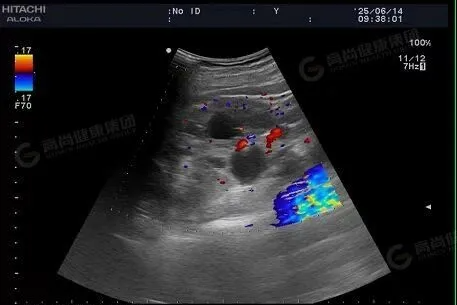

「阿姨,你血糖偏高,平时饮食要少油盐。」「叔,身体不舒服不能硬扛,我帮你开个免费检查单。」在义诊现场,专家们耐心地询问村民们的病史和日常身体状况,仔细的为他们测量血压,进行听诊、腹部触诊等检查,并针对村民们的健康问题给出了专业的诊断和治疗建议。对于一些需要进一步检查和治疗的患者,专家们还详细地为他们讲解了就医流程和注意事项,并现场开出免费 B 超和心电图检查单。

除了常规血糖血压检测之外,还增设免费心电图、超声检查。「这些检查都是免费的,虽然人很多,我也愿意等。」村民罗大爷说道。